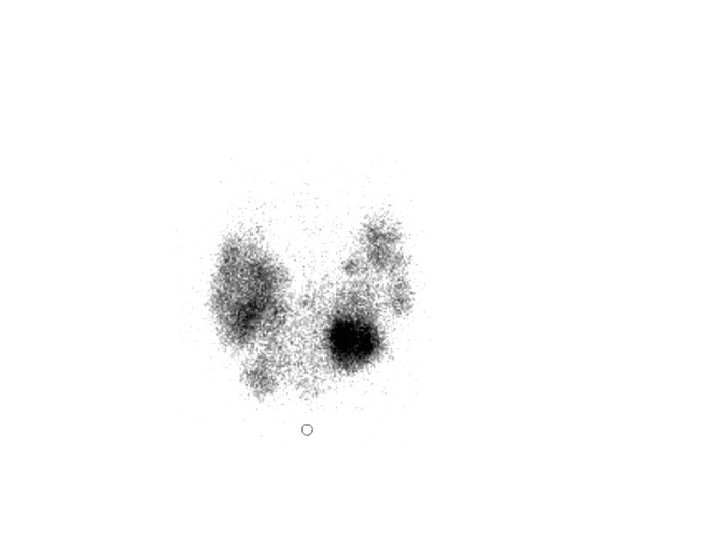

Scintigraphie Image scintigraphique de la thyroïde

Examens morphologiques : A- Scintigraphie ou cartographie de la thyroïde : Une thyroïde normale réalise une image en papillon prétrachéale de fixation régulière et homogène.

Résultats de la scintigraphie : Thyroïde de fixation normale Thyroïde hypofixante ( hypothyroïdie) Thyroïde hyperfixante ( hyperthyroïdie) Thyroïde augmentée de volume mais de fixation normale ( goitre simple).